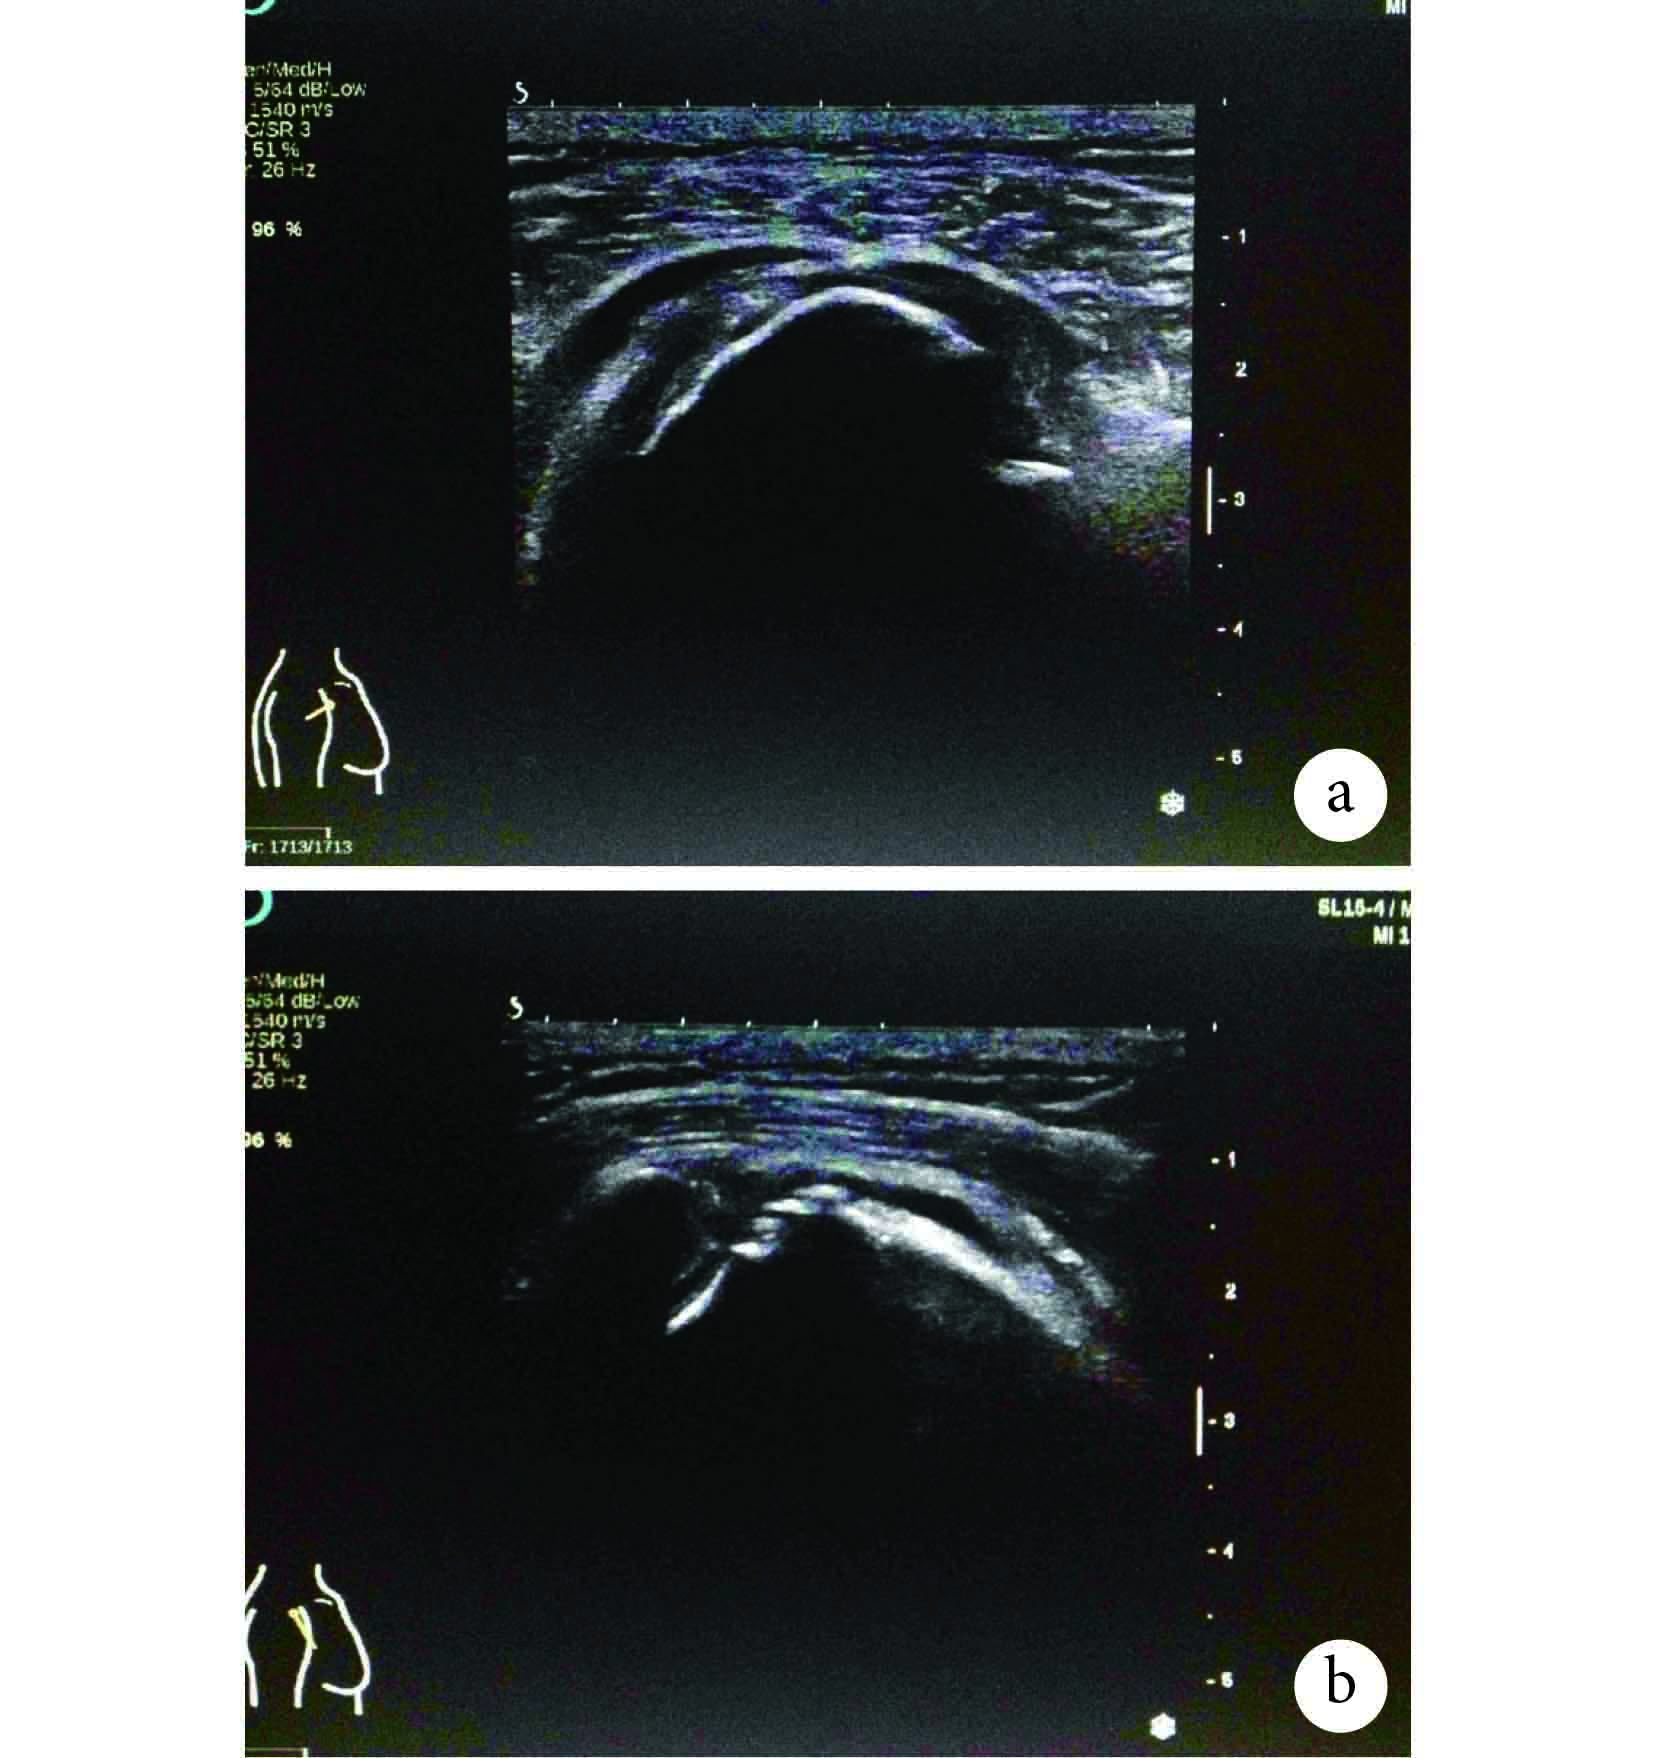

52 例臨床疑似岡上肌腱損傷患者經超聲檢查診斷,其中 37 例存在岡上肌腱病變。37 例患者中男 13 例,女 24 例;年齡 25~67 歲,平均 47.5 歲;左肩側 6 例,右肩側 31 例,為右利手多發。包括以下 2 類:① 岡上肌腱退行性、黏液性變的非感染性肌腱炎共 20 例,其中岡上肌腱鈣化性肌腱炎 10 例;② 岡上肌腱撕裂 17 例,其中完全撕裂 4 例,部分撕裂 13 例,見圖 1、2。以 MRI 結果為參照,超聲檢查發現岡上肌腱損傷的靈敏度為 85.0%,特異度為 75.0%,陽性似然比為 91.9%,陰性似然比為 60.0%,符合率為 82.7%,見表 1。其中 12 例行關節鏡手術示患者均存在不同程度岡上肌腱撕裂,10 例術前超聲有相對應提示;1 例關節鏡下見近止點處局灶撕裂,超聲未檢出,回顧分析圖像是因為未充分暴露止點;1 例超聲檢查為完全撕裂,關節鏡檢查評估為部分撕裂,可能因該部分撕裂病灶臨近對側未斷裂邊緣,且周圍肌腱各向異性偽象所致;1 例超聲診斷鈣化性肌腱炎伴部分撕裂,關節鏡未見鈣化灶,分析可能為陳舊性撕裂后改變影像。

圖1

右肩岡上肌腱完全撕裂超聲聲像圖 長軸切面缺損 1.5 cm,短軸切面缺損 1.7 cm,并肩峰下滑囊積液;a. 岡上肌腱短軸;b. 岡上肌腱長軸